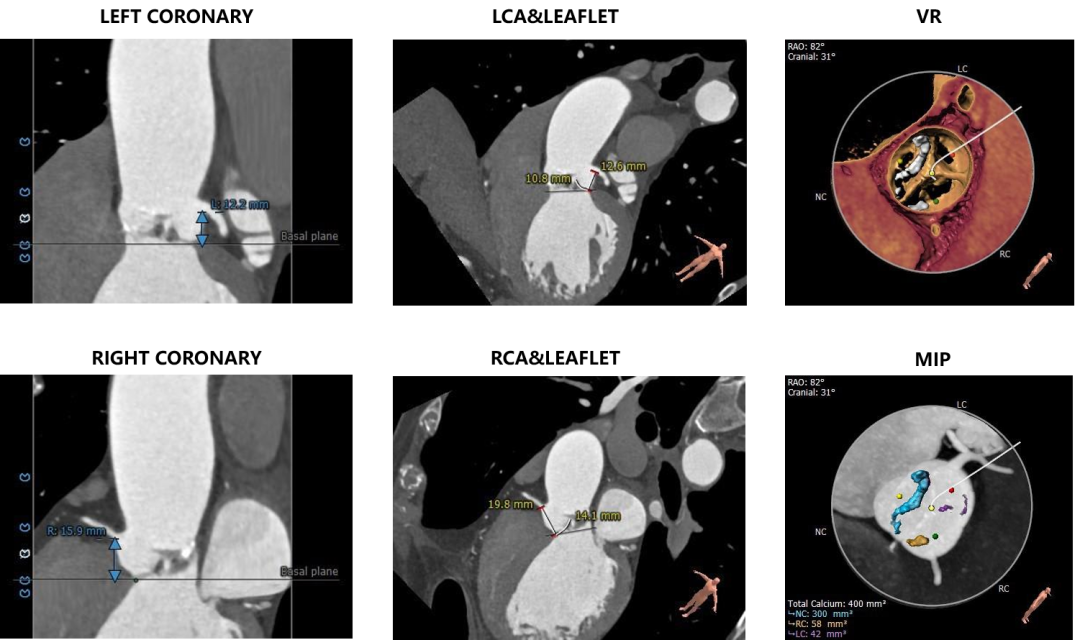

• 术前CT显示为Type 1型二叶式主动脉瓣,瓣叶严重增厚,左右冠窦瓣叶融合并形成纤维嵴。中度钙化,钙化分布不均匀,最严重处为无冠窦瓣叶处。

• 左右冠开口高度可,左右冠瓣叶长度<左右冠开口到左冠瓣叶附着缘距离。

主动脉根部测量

冠脉高度、瓣叶长度及钙化测量

瓣环上测量